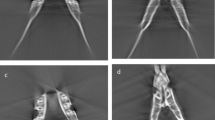

For linear measurements, CBCT images were oriented as shown in Fig. 3, with the Frankfurt plane being positioned parallel to the horizontal plane. Three linear measurements (L1, L2 and L3) were then taken (Fig. 4).

For volumetric calculations, a 3D scanner (iTero; Align Technologies, San Jose, Calif. USA) was used to obtain STL surface models of the twelve condyles (Fig. 5). For the scanning procedure, condyles were mounted on a base made of casting wax. The operator scanned the structure starting at the condyle’s head while the opposing part was inserted into the wax base. Once this part was successfully scanned, the head was inserted in the wax base hence allowing the scanning of the opposing part. Each surface model was imported and superimposed onto its corresponding DICOM reconstruction using the manual superimposition tool included in the Dolphin Imaging® software (Fig. 6). Condyles were isolated on the CBCT render volume using the surface models as reference, to reproduce the exact dry condyle structure. Soft tissues were removed from the CBCT images using the software’s sculpting tool. The volume of the isolated structure was calculated by the software’s automatic volume measuring tool.